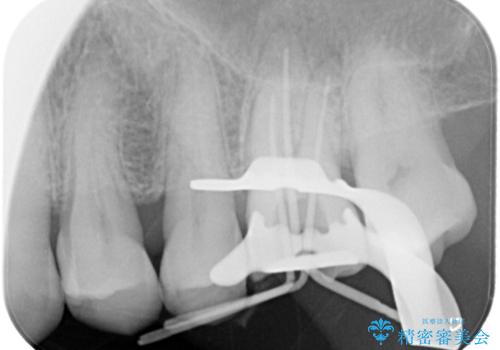

根管治療にはラバーダムシートをつけて行うことが大切です。マイクロスコープを使用し治療を行いました。治療後、歯の痛みは消失し、とても満足していただきました。